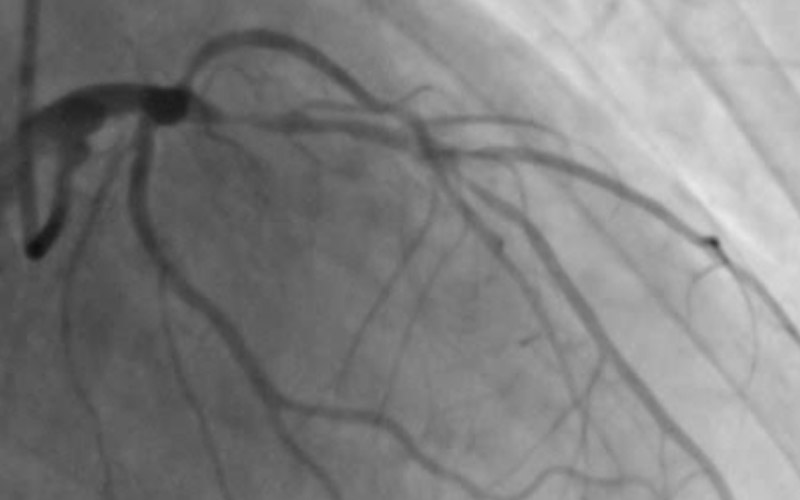

وقام د. السيد محمد فرج أستاذ القلب والقسطرة القلبية بجامعة الزقازيق، والمشرف الفني على قسم القسطرة بإجراء قسطرة قلبية وتركيب 3 دعامات إنقاذ الحياة، لحالة تعاني من احتشاء بعضلة القلب وقصور حاد بالشريان التاجي.

ونوضح بــ"الصور والفيديو" الشرايين التاجية قبل وبعد تركيب الدعامات، وبالفيديو نوضح الموجات فوق الصوتية، لحالة عضلة القلب قبل تركيب الدعامات.